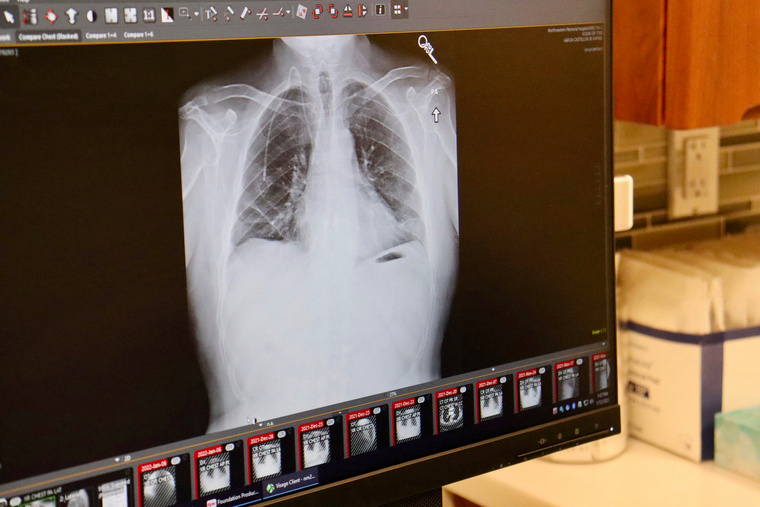

Ils seront appelés à faire deux scanners thoraciques à faible dose à un an d'intervalle, puis tous les deux ans, et se verront également proposer un sevrage tabagique.